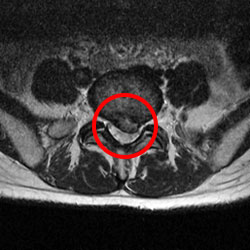

術前

ヘルニアが神経を圧迫しています。

MRI

MRI